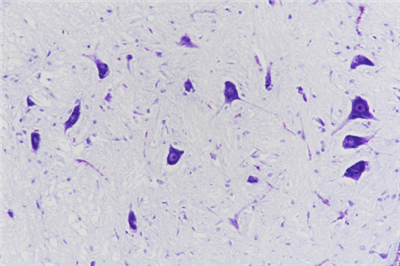

簡要描述:尼氏染色:即Nissl染色法,用來鑒定神經(jīng)元胞體中的尼氏體,是最常用的神經(jīng)細(xì)胞染色,在該染色中,尼氏小體清晰可見,可區(qū)分軸突和樹突等。

神經(jīng)元細(xì)胞體包括一個具有皺褶核膜的大細(xì)胞核、稀疏的染色質(zhì)和一個明顯的核仁。在細(xì)胞體中細(xì)胞質(zhì)是尼氏顆粒,即能夠代表粗面內(nèi)質(zhì)網(wǎng)并在很多神經(jīng)元中產(chǎn)生特異的斑點狀嗜堿性表現(xiàn)的嗜堿性顆粒。尼氏顆??梢杂煤芏嗳旧珌盹@示如中性紅、亞甲基藍(lán)、甲苯胺藍(lán)和甲基紫等。染色的變異、pH和分化的時間使一些染色既可以僅突出尼氏物質(zhì),也可以顯示神經(jīng)元的細(xì)胞核和神經(jīng)膠質(zhì)。各種神經(jīng)細(xì)胞內(nèi)都含有尼氏體,但其形狀、數(shù)量、分布位置常常不同。尼氏體也存在于樹突中,但不在于軸突和胞體的軸丘。尼氏體會因為生理狀態(tài)的變化而變化,尼氏體是神經(jīng)元內(nèi)合成蛋白質(zhì)合成的重要部位,當(dāng)神經(jīng)元受到刺激后,胞體內(nèi)的尼氏體會明顯減少。通常尼氏體能被堿性染料如硫堇、亞甲藍(lán)、甲苯胺藍(lán)和焦油紫等染料染成紫藍(lán)色。

染色結(jié)果:尼氏體呈紫色、細(xì)胞核呈藍(lán)色